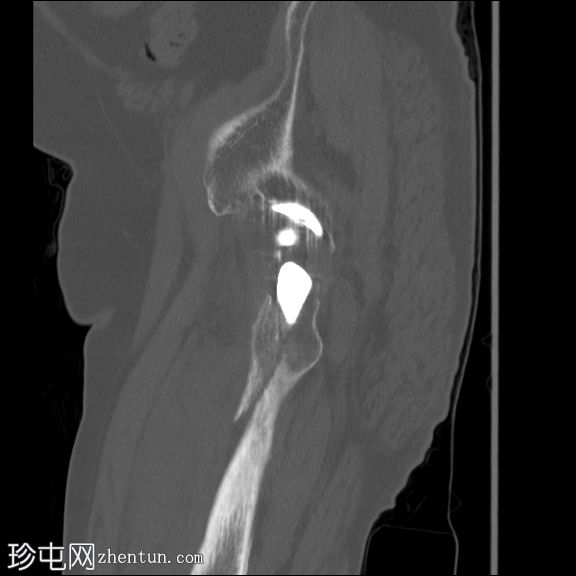

CT扫描

矢状骨窗

左股骨内存在轻微移位的假体周围骨折。

左大腿前部可见大量肌肉,可能提示血肿。但未见明显可引流积液。